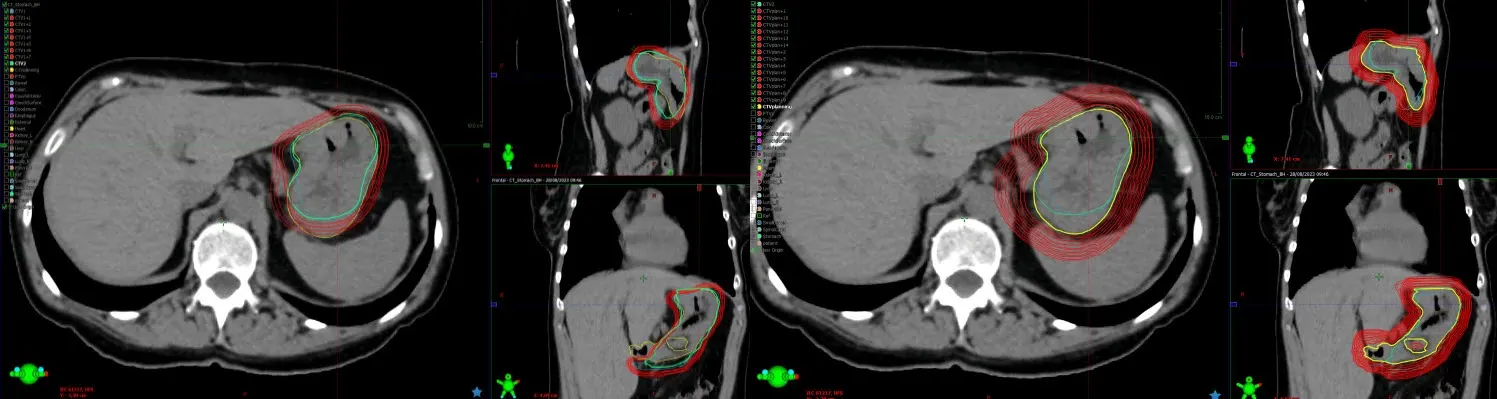

Image description goes hereCBCTs from treatment session 1

CBCTs from treatment session 1 showing, in 1-mm increments, margin expansions necessary to cover CTV for adaptive treatment (left panel) and non-adaptive treatment (right panel). Margins of 4 mm were sufficient to achieve 95% coverage for the adaptive session, but for non-adaptive treatment a margin of 12 mm would be required. (From Figures 1 and 2, Tison et al.)